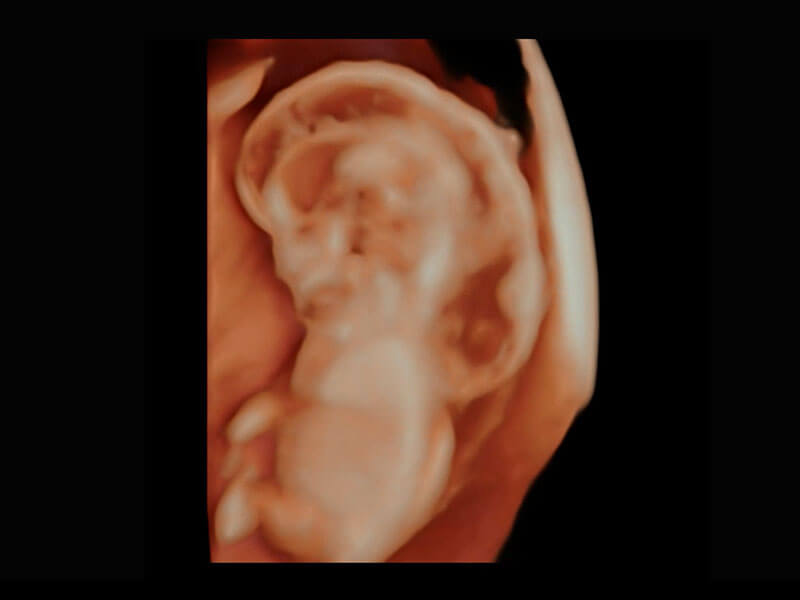

高分辨率容积成像-早孕胎儿

光影成像-孕囊